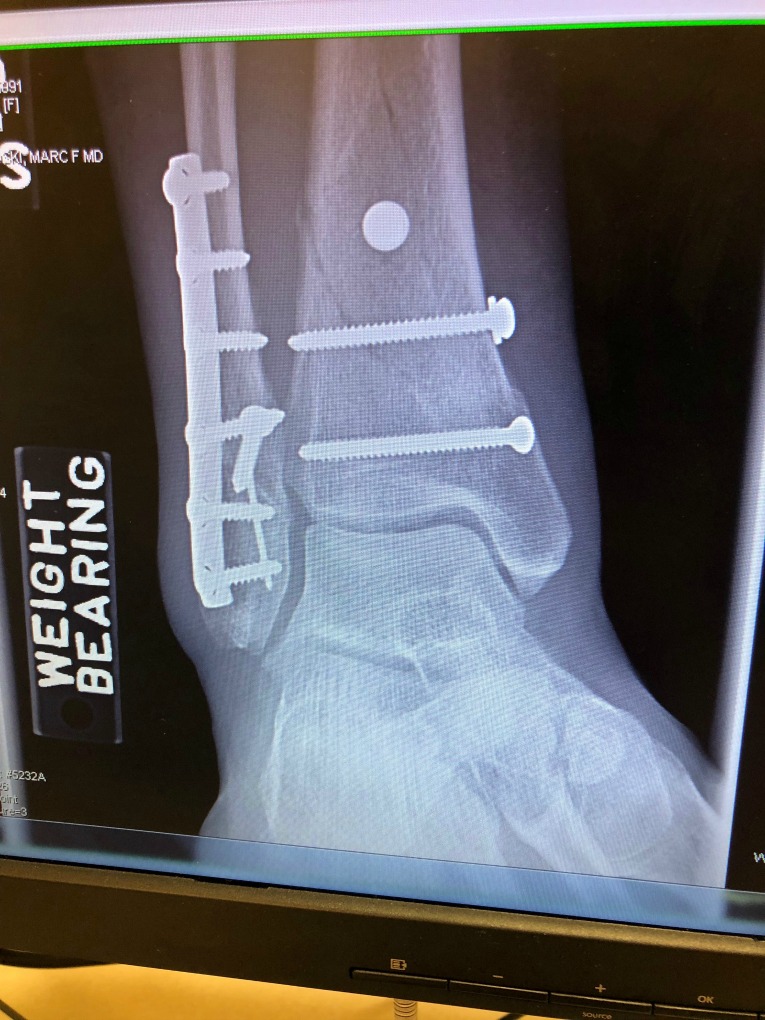

PT was great and I’m officially out of the boot! The appointment with the surgeon also went well- they took new x-rays, and though you can still see a few of the fractures, the joint is healing really well.

The surgeon said the fractures will still show up on X-rays for another 6 weeks or so. He recommended two more weeks before I could start using the Alter-G/Zero Gravity treadmill. Then another 4 more weeks of PT before I might be able to run on the treadmill a little bit; i.e. 1 minute on, 1 minute off kind of thing- a very slow build.